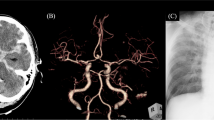

Regarding the incidence of DCI-related infarctions in our collective, we found no significant differences between the study groups (27% in the control group vs. 25% in the APT group, P = 0.875; Table 1). A detailed analysis of the infarct characteristics showed comparable patterns with respect to the number of vascular territories involved, the location or the laterality (Table 1). Although the median lesion volume did not differ significantly between the groups, we found a statistical trend toward higher absolute values in the control group 78.5 cm3 (IQR 24.7–282.6) vs 33.7 cm3 (IQR 6.1–107.5) in the APT group (P = 0.090). The lesion overlay plots of patients with DCI-related infarctions are shown in Fig. 1. It visually appeared that the patients in the control group developed more often larger areas of infarction, especially in the left hemisphere (Fig. 1a). In the lesion overlap image of the two subgroups of APT patients (aspirin mono APT vs. DAPT), it visually appeared that patients with DAPT had especially small lesion overlaps (Fig. 1b). This impression could also be statistically supported, because the median lesion volume was significantly smaller in the DAPT subgroup (14.3 cm3 (IQR 5.1–57.8) than in the control group (78.5 cm3 (IQR 24.7–282.6), P = 0.011).

Lesion overlay plots showing DCI-related cerebral infarctions in the control and the APT group (a) and, in a further subgroup analysis, infarct lesions inpatients receiving aspirin monotherapy or dual APT (aspirin plus clopidogrel) (b). The color bar indicates the number of overlapping lesions (minimum n = 2)

Due to the discrepancy between improved outcome and absence of overall CVS and DCI reduction in patients with post-interventional APT, we performed a detailed analysis of the severity and the distribution patterns of angiographic CVS and of DCI-related infarction. Interestingly, we found no significant differences between the groups with regard to the severity, the vessels or vascular territories affected, or any other investigated parameter. The analysis of the infarct lesion volumes demonstrated a non-significant statistical trend toward a higher lesion volume in the control group, and the descriptive lesion analyses in our study indicated that the patients in the control group developed more often larger infarctions with a predominance in the left hemisphere. Moreover, the results of the subgroup analysis suggest that especially the DAPT treatment might have a protective effect. The beneficial effect of APT on functional outcome in our cohort might therefore be mediated by the reduction of the lesion size, especially when DAPT was administered which was the case in the majority (2/3) of our patients receiving antiplatelet medication. In this context, it is interesting that PCT examinations in the APT group demonstrated DCI-related cerebral hypoperfusion significantly less often compared with the control group.